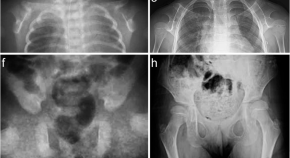

Andrea Superti-Furga, Ron Wevers, Clara van Karnebeek, Luisa Bonafé and colleagues identify mutations in NANS, which encodes the sialic acid synthase, in nine individuals with severe infantile-onset developmental delay and skeletal dysplasia. They describe abnormal metabolites accumulating because of deficient NANS enzyme activity and show that impaired sialic acid synthesis in zebrafish perturbs skeletal development, which can partially be rescued by supplementation with exogenous sialic acid.